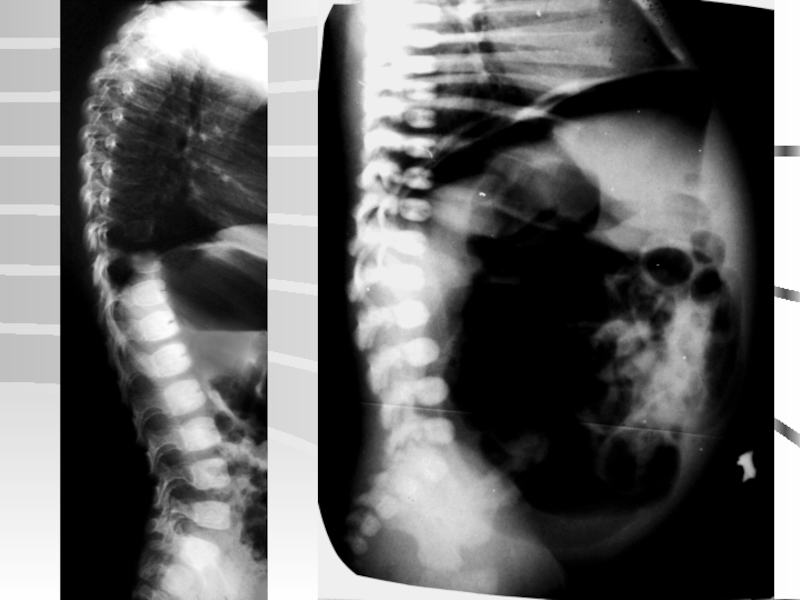

Слайд 58Пациент О. 4 лет

Оперативное лечение злокачественно прогрессирующих ювенильных сколиозов

100°

31°

По наблюдению

Михайловского М.В.,

НИИТО, 2005

Пациент О. 4 летОперативное лечение злокачественно прогрессирующих ювенильных сколиозов100°31°По наблюдению Михайловского М.В.,НИИТО, 2005